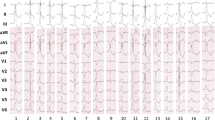

The electrophysiological study was performed with the patient in a fasting state, under local anesthesia with mild-to-moderate sedation. Figure 1 shows three examples of the usual placement of the electrophysiological catheters during the electrophysiological study. Twelve-lead surface ECG and intracardiac electrogram recordings were displayed and stored on a computer-based digital amplifier system (Prucka Systems, General Electric Healthcare Inc., Milwaukee, WI, USA, or WorkMate, St. Jude Medical Inc.). During sustained atrial tachycardia or flutter, we mapped the tachycardia using conventional methods and a 3D electroanatomical system. In cases of atrial flutter, we placed a crista catheter or a deflectable duodecapolar catheter in the RA and recorded the intracardiac electrogram in the anterior and posterior portions of the RA lateral wall, before 3D mapping was performed. When the two sequences of the atrial electrogram were in the same direction, we considered cavotricuspid isthmus (CTI)-dependent atrial flutter to be highly probable, whereas when the two sequences were in opposite directions, we judged there to be a high probability of atypical atrial flutter, including scar-related or dual-loop atrial flutter. Conventional methods included activation mapping and entrainment pacing. As mapping catheter for 3D electroanatomical mapping, we used a 20-pole deflectable crista catheter in 12 patients (crista group; Fig. 1a), a 20-pole deflectable lasso catheter (Biosense Webster Inc.) in 12 patients (lasso group; Fig. 1b), and a 4-pole deflectable ablation catheter (ThermoCool Catheter, Biosense Webster Inc.) in 11 patients (ablation group; Fig. 1c) as a mapping catheter. The crista catheter is 7 French in size and has 20 1-mm electrodes with 1-3-1 mm inter-electrode spacing and a D-shaped deflection which is suitable to be positioned along the crista terminalis. An SL-1 or SR-0 sheath (St Jude Medical Inc.) was used to introduce the mapping catheter, according to the operator’s preference. During the clinical tachycardia, an activation map and a voltage map were created with the mapping catheter. The 3D mapping time and points were measured and recorded. After activation and voltage mapping, in cases of macroreentry tachycardia, entrainment pacing was performed at the potential critical isthmuses. After the origin and mechanisms of tachycardia had been identified using conventional methods and the 3D electroanatomical mapping system, radiofrequency energy was delivered at the points of earliest electric activity in cases of focal atrial tachycardia, or the slow-conducted critical isthmus in cases of macroreentrant tachycardia. The maximum power output of the radiofrequency energy was 40 W using a 3.5-mm irrigated-tip ablation catheter (ThermoCool Catheter, Biosense Webster Inc.).

In 13 of the 20 patients with atrial flutter on the surface ECG, we recorded and compared the sequence of the atrial electrograms in the anterior and posterior portions of the RA lateral wall (Fig. 2). In four patients, the two sequences of the atrial electrogram had the same as high-to-low or low-to-high direction. In three of these four patients, the two sequences were in high-to-low; the tachycardias were confirmed by 3D electroanatomical mapping as counterclockwise CTI-dependent atrial flutter. In one of these four patients, the two sequences were in low-to-high; the tachycardias were confirmed as clockwise CTI-dependent atrial flutter (Fig. 3). In these four patients, the atrial flutter was terminated by the CTI block. In nine patients, the two sequences of the atrial electrogram were in opposite directions (high-to-low and low-to-high; Fig. 4). In five of these nine patients, the tachycardias were confirmed by 3D electroanatomical mapping as scar-related atrial flutter with a reentry circuit around the right atriotomy scar; the atrial flutter was terminated by linear ablation between the inferior margin of the scar and the inferior vena cava. In the other four patients, the tachycardias were confirmed by 3D electroanatomical mapping as dual-loop atrial flutter, including scar-related and CTI-dependent atrial flutter, and the atrial flutter was terminated by the CTI block and the linear ablation between the inferior margin of the scar and the inferior vena cava. When we carefully recorded the electrogram around the RA lateral wall with a crista catheter or a duodecapolar catheter during tachycardia in patients with scar-related atrial flutter, we were able to record the turnaround point of electric activation at the inferior margin of the right atriotomy scar (Fig. 5). In this case, atrial flutter was terminated by linear ablation between the turnaround point and the inferior vena cava.

Clockwise cavotricuspid isthmus-dependent atrial flutter in a 40-year-old female patient who underwent total correction of tetralogy of Fallot. a Right anterior oblique fluoroscopic views show the crista catheter (arrow) located in the posterior and anterior portions of the RA lateral wall, respectively. b Both electrograms from the posterior and anterior portions of the RA lateral wall show low-to-high sequence. c Three-dimensional activation map in left anterior oblique view. White arrows indicate electric activation sequence. White and brown dots indicate ablation sites and the tricuspid annulus, respectively

Scar-related atrial flutter in a 31-year-old female patient who underwent atrial septal defect repair. a Right anterior oblique fluoroscopic views show the crista catheter (arrow) located in the posterior and anterior portions of the RA lateral wall, respectively. b The electrogram from the posterior portion of the RA lateral wall shows low-to-high sequence, whereas the electrogram from the anterior portion shows high-to-low sequence. c Three-dimensional activation map in right anterior oblique view. White arrows indicate electric activation sequence. White, gray, and red dots indicate the tricuspid annulus, scar tissue, and ablation sites, respectively